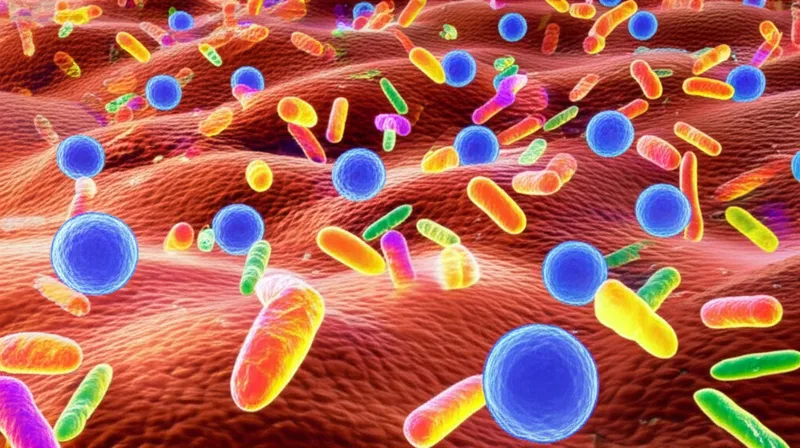

infectionsnoun

/ɪnˈfɛkʃənz/

""Washing your hands often helps prevent the spread of infections." "

Se laver souvent les mains permet d'éviter la propagation des infections.